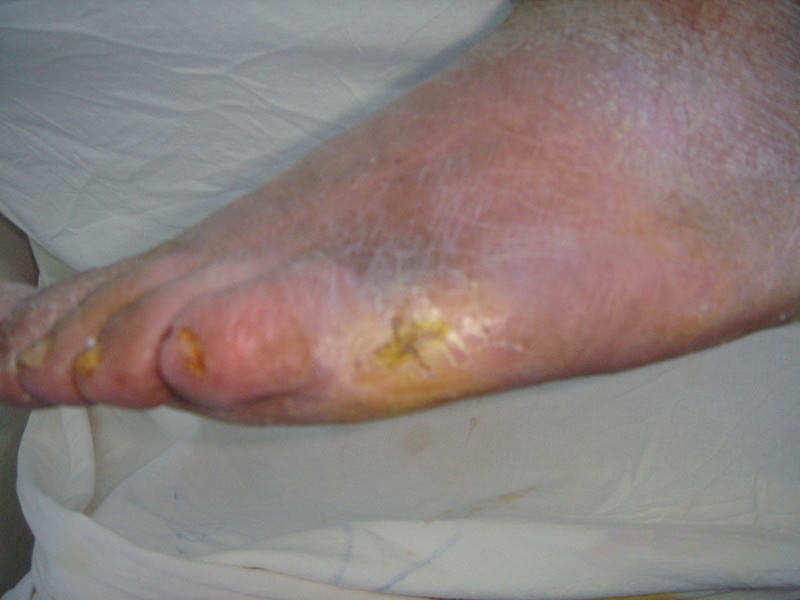

(8)出现红斑、局部温度升高、胼胝形成可能为临近破溃的组织损伤。

①及时检查和尽早发现足部是否有水疱、裂口及擦伤等。因为足部溃疡感染及坏疽都是从微小创伤引起的,一旦发现,应立即到医院就诊。

②保持足部皮肤完整清洁。脚上表皮擦破时,不要用指甲去撕,而应立刻用香皂、酒精等消毒清洁,再以消毒过的绷带包扎,不需敷用药膏。如果使用鞋垫,应选大小适中的鞋垫,以免皮肤磨损受伤。如有以下各种情形时,应立刻请医生诊治:淤血、肿胀、发红、发热等。